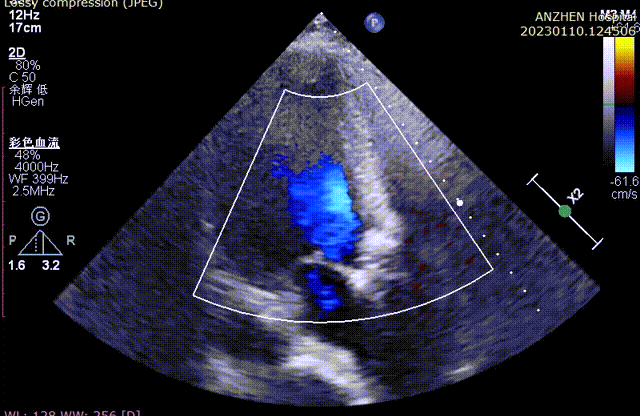

超声心动图提示:主动脉瓣脱垂并重度关闭不全,二尖瓣脱垂并中-重度关闭不全,左心增大,升主动脉轻宽,三尖瓣中度反流。EF:55%。

术前超声

术后超声